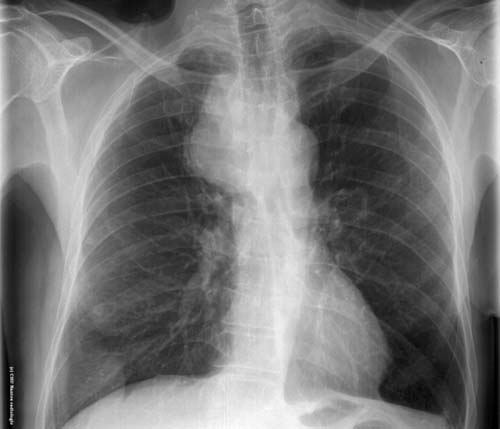

Syndrome médiastinal